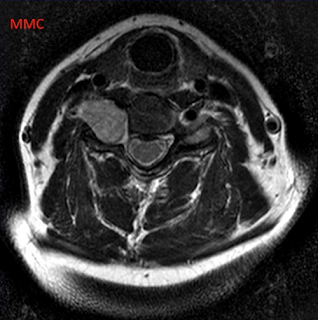

cas n°3

3- Neurinome cervical droit